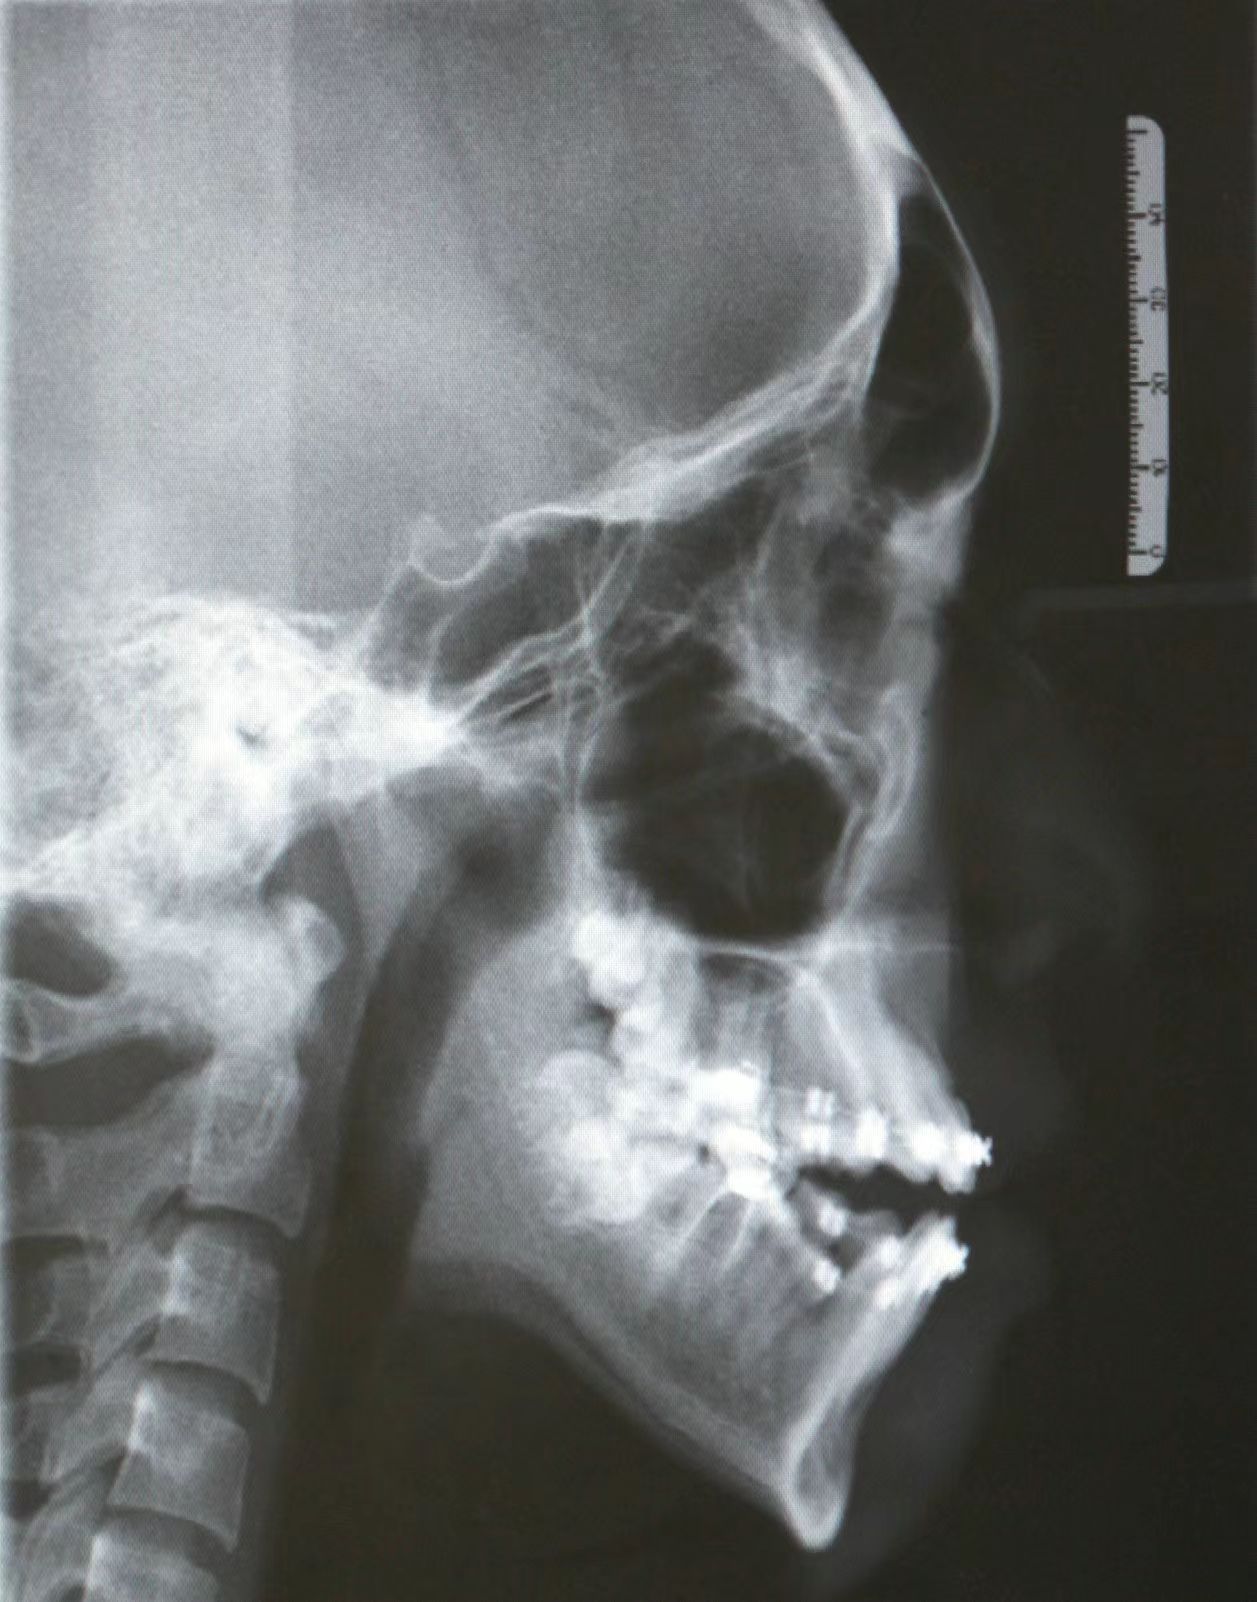

情况:不接受外科手术,在当地做了1年半的矫治,遇到困难无法进行。由外地正畸同行推荐来上海寻求非手术矫治的二手病例。武广增老师接收时的错合畸形情况,呈现严重的骨性反合偏合及侧方开合(图1-图10)。由于推荐其去口腔医院接受正颌外科手术遭到拒绝,武广增老师通过专业的检查、分析,制定一套详细的治疗计划,采用了磨牙推进器技术、武式辅弓技术等特色正畸手段获得明显效果(图2-1~图2-9)。治疗结束后也拍摄了相关照片(图3-1~图3-9)。

矫治前

图1